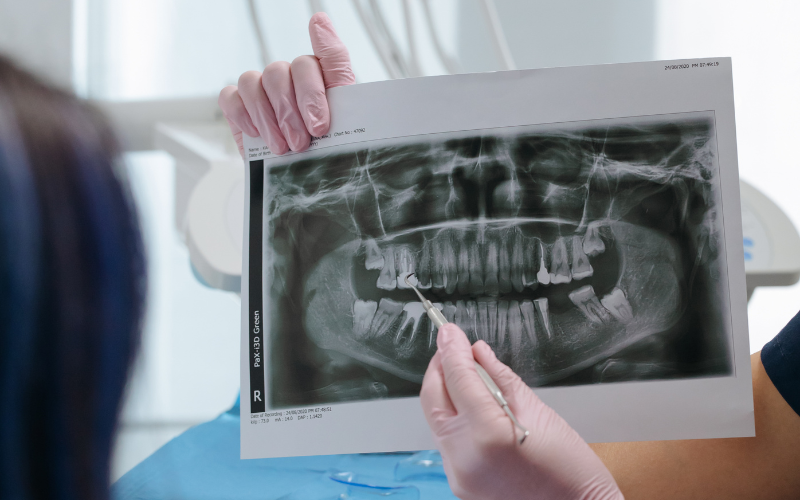

One of the most exciting advancements in modern dentistry is the use of digital technology. With digital dentistry, dentists can now design and simulate a patient’s future smile before any treatment even begins. Using digital scanning, 3D imaging, and computer-assisted design systems, dentists can analyze the patient’s teeth, bite, and facial proportions with exceptional accuracy.

The digital smile design technology allows patients, especially women who are often very conscious about aesthetics, to visualize the expected results of their smile makeover in advance. This approach improves communication between dentist and patient, reduces treatment uncertainty, and ensures highly precise outcomes.

Digital tools also make procedures faster, safer, and more comfortable. Traditional messy dental impressions are increasingly replaced by digital scans, and restorations such as veneers or crowns can be designed with remarkable precision.